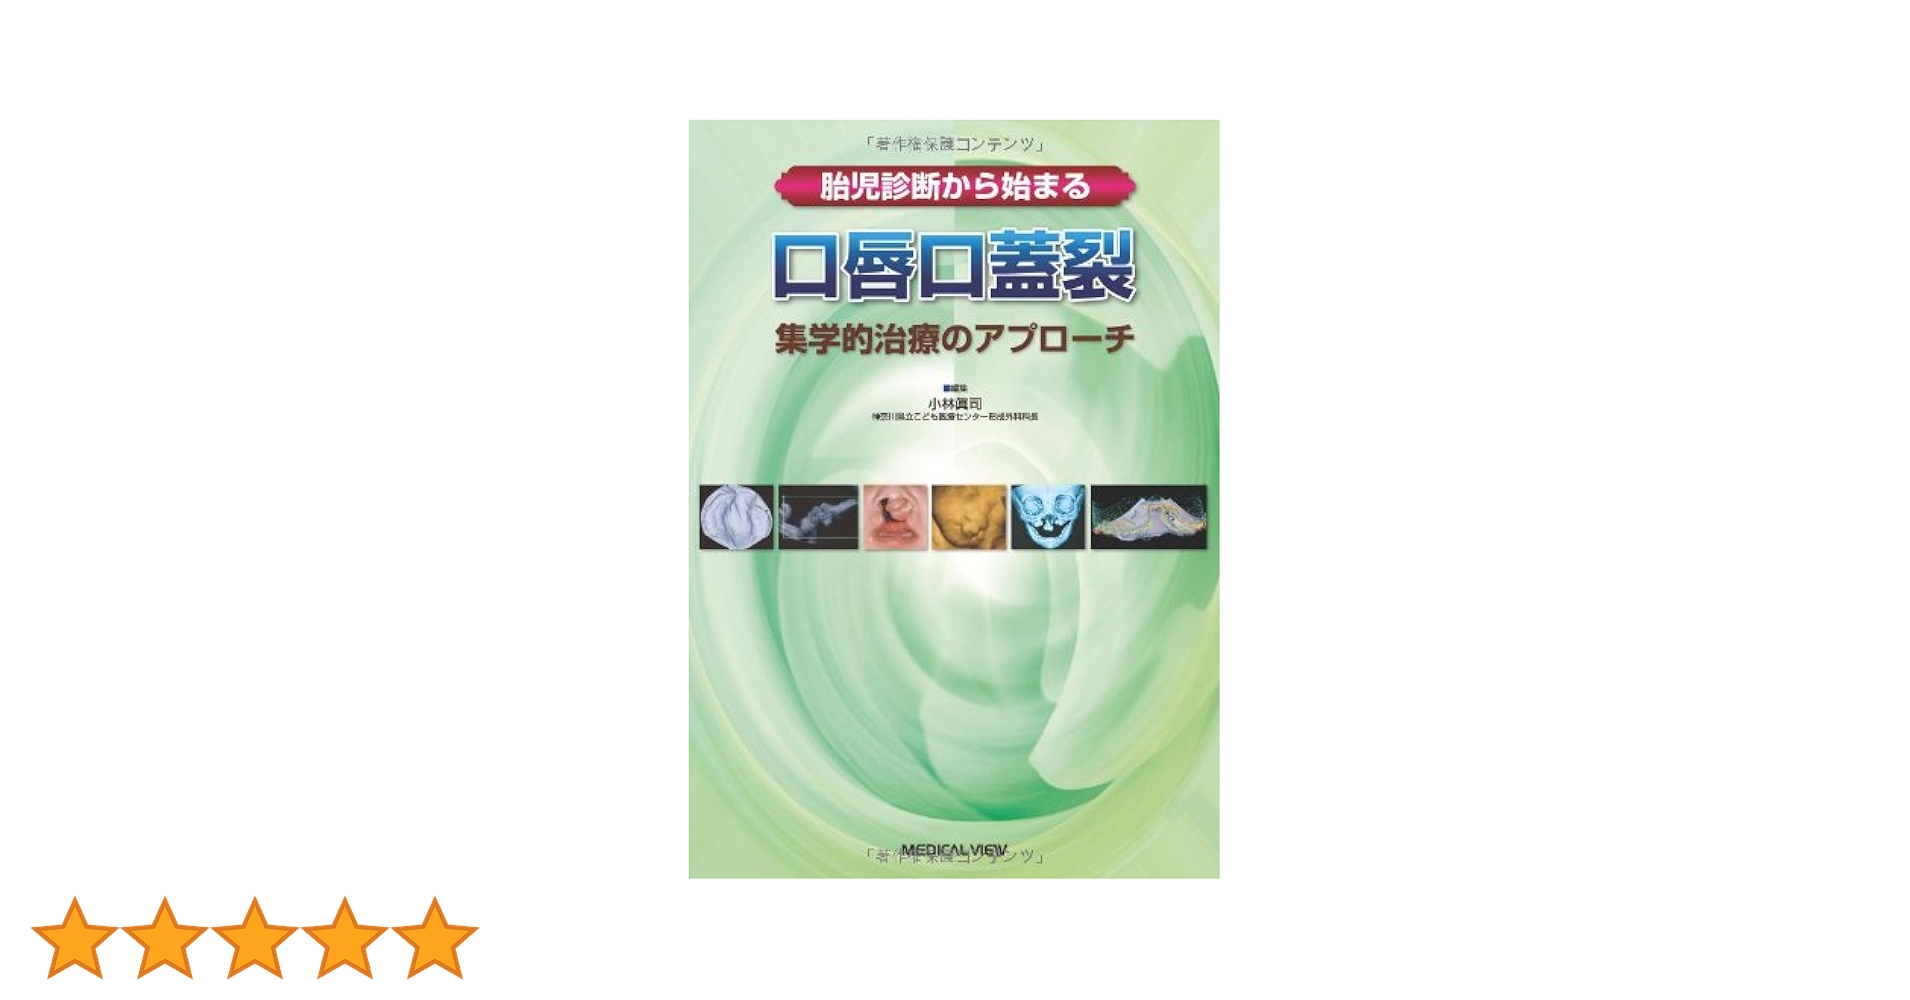

胎児診断から始まる口唇口蓋裂 集学的治療のアプロ-チ/メジカルビュ-社/小林眞司(単行本) 胎児診断から始まる 口唇口蓋裂−集学的治療のアプローチ | 小林の詳細情報

胎児診断から始まる 口唇口蓋裂−集学的治療のアプローチ | 小林。口唇裂・口蓋裂治療の手引 改訂第3版 |本 | 通販 | Amazon。0161-726x1024.jpg。

口唇口蓋裂の手術治療② 口蓋裂 | メディカルノート

著者名:小林眞司

出版社名:メジカルビュ−社

発売日:2010年03月10日

ISBN:9784758310659

商品状態:可

◆◆◆カバーに破れがあります。【中古】 病気の子どもの理解と援助。印押しがあります。整体DVD計4枚【大澤訓永の最新!BMK頭痛・頸肩テクニック】。中古ですので多少の使用感がありますが、品質には十分に注意して販売しております。【中古】 最強の免疫 ルネ・カントンの海水療法/日本文芸社/日下部喜代子。迅速・丁寧な発送を心がけております。【中古】 村上式カイロドクター二十一世紀への挑戦 コミック版/世界出版(港区)/山本良行。【毎日発送】

※商品画像は参考画像です。整体DVD【完結版 静脈整体STARテクニック】【自動操法プログラム】星野高宏。お届けする商品は中古品のため、帯の有無や商品状態に差異がある場合がございます。【中古】 我が家の秘伝薬草、ハーブ/上毛新聞社/田所作太郎。あらかじめご了承ください。【中古】 ストレスウォッチング 現象とメカニズムと克服法/佼成出版社/平井富雄。

口唇口蓋裂の手術治療② 口蓋裂 | メディカルノート

著者名:小林眞司

出版社名:メジカルビュ−社

発売日:2010年03月10日

ISBN:9784758310659

商品状態:可

◆◆◆カバーに破れがあります。【中古】 病気の子どもの理解と援助。印押しがあります。整体DVD計4枚【大澤訓永の最新!BMK頭痛・頸肩テクニック】。中古ですので多少の使用感がありますが、品質には十分に注意して販売しております。【中古】 最強の免疫 ルネ・カントンの海水療法/日本文芸社/日下部喜代子。迅速・丁寧な発送を心がけております。【中古】 村上式カイロドクター二十一世紀への挑戦 コミック版/世界出版(港区)/山本良行。【毎日発送】

※商品画像は参考画像です。整体DVD【完結版 静脈整体STARテクニック】【自動操法プログラム】星野高宏。お届けする商品は中古品のため、帯の有無や商品状態に差異がある場合がございます。【中古】 我が家の秘伝薬草、ハーブ/上毛新聞社/田所作太郎。あらかじめご了承ください。【中古】 ストレスウォッチング 現象とメカニズムと克服法/佼成出版社/平井富雄。

オススメ度 4点

現在、2960件のレビューが投稿されています。